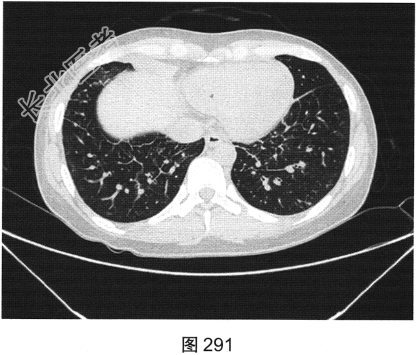

- [材料题] 患者女性,43岁,因“确诊肺低分化腺癌1周”就诊。患者于2014年11月无明显诱因出现咳嗽、咳痰,无胸闷胸痛,无咯血,无发热、乏力、体重减轻等。自服中药治疗,止咳效果尚可。2015年4月22日在山海关人民医院行胸部CT:显示①慢性支气管炎继发感染,建议结合临床及病史考虑;②右侧中间段支气管及中叶支气管壁增厚、管腔狭窄伴右肺中叶阻塞性肺不张,右侧肺门及纵隔多发淋巴结增大,建议增强扫描。后补做增强CT:右肺中叶支气管增厚,管腔狭窄伴阻塞性肺不张,考虑右侧中心型肺癌伴纵隔多发淋巴结增大,建议行支气管镜检查。支气管镜取活检病理:示低分化腺(右肺中叶)癌,建议做免疫组织化学检测,以进一步明确诊断。于北京肿瘤医院行PET/CT检查:①右肺中叶支气管起始部位高代谢结节,符合中心型肺癌表现;右肺中叶部位阻塞性不张,不张肺内高代谢结节,倾向肺内转移;双肺多发转移结节;双锁骨上区、左胸肌间、纵隔及双肺门多发淋巴结转移。②脑部未见明显高代谢征象,建议行增强MRI检查。③双叶甲状腺炎性或非特异性摄取,建议行B超及甲状腺功能检查。患者精神状态良好,体力、食欲、睡眠均正常,体重无明显变化,大便、排尿正常,为进一步检查及治疗,门诊以“肺癌”收入院。2015年5月5日在我院行CT检查,如图288~图295所示。